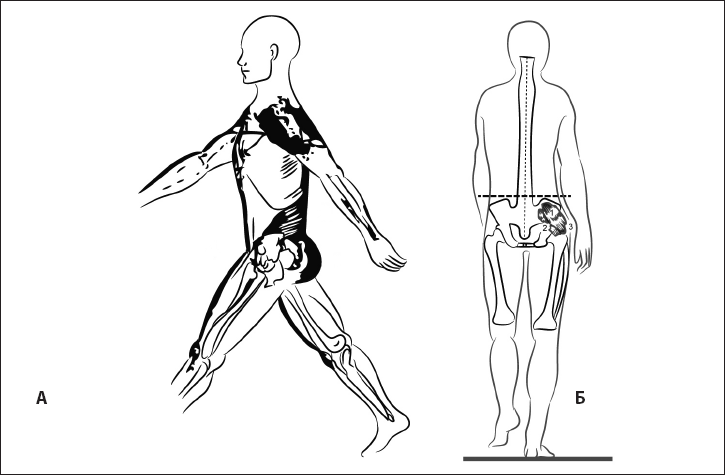

У взрослого человека он постепенно переходит в рефлекс поддержания головы в вертикальном положении, а мышцы-разгибатели формируют заднюю МФЦ (рис. 19).

Рис. 19. Задняя миофасциальная цепь.

Эта цепь позволяет поддерживать тело в вертикальном положении в статике и при ходьбе. Сокращаясь одномоментно, мышцы с одного конца цепи поддерживают баланс мышечной силы на другом.

С последующим развитием нервной системы задняя МФЦ вытягивается и начинается от подошвенной поверхности пальцев стопы.

Если пальцы стоп в ходьбе не участвуют, то сложная координационная мышечная цепь рассыпается на отдельные участки, вызывая избыточное сокращение в отдельных регионах позвоночника и конечностей.

Так возникает нарушение осанки в виде верхне-перекрещенного, нижне-перекрещенного и слоистого синдромов и нестабильность нескольких регионов – в динамике (рис. 20).

Рис. 20. Неоптимальность динамики. Нарушение осанки как результат снижения функции мышц таза.

Визуальные признаки нарушения этого рефлекса у взрослого: сидя или стоя появляется желание опустить голову, а при ходьбе – тщательно рассматривать дорогу. Длинные экстензоры очень часто бывают нарушенными, поскольку имеют места прикрепления в межлопаточной области, а этот регион часто нестабилен.

Патобиомеханика: возникают заднее смещение головы, наклон таза назад, избыточное сгибание в коленных суставах (рис. 21).

Рис. 21. Неоптимальная статика. Заднее смещение головы, наклон таза назад и избыточное сгибание в коленных суставах как результат нарушения формирования рефлекса разгибания.